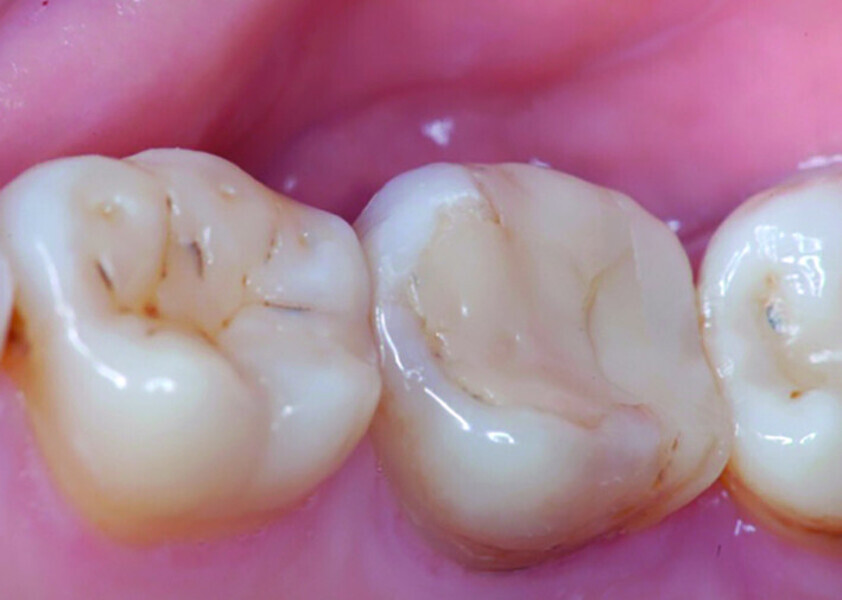

Fig. 1: Pre-op occlusal view.